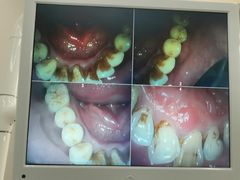

• -牙博士口腔品牌连锁(杨浦店)

fairy7_7 | 22-07-28

报错